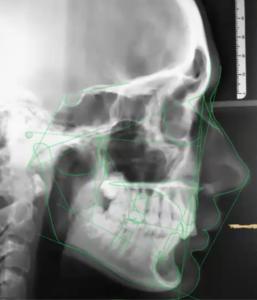

Precision du clin-check

Si vous choisissez un traitement par aligner, confiez-nous le code de votre portail fabriquant et nous vérifions vos set-up.

Car un traitement par gouttière ne se termine jamais comme montré sur la pré-visualisation. « It is not about the plastic, it’s about the plan »

Donc peaufinez vos attachements à ajouter ! et surtout sachez que dans 80% des cas il y aura besoin d’ajouter des gouttières de finition, des auxiliaires (qhx?) voire un traitement hybride (sectionnel multi-attaches puis aligners).

Augmentez votre taux de réussite avec Ortho Spirits : La planification experte qui simplifie vos traitements. Libérez tout le potentiel des aligneurs grâce à nos méticuleux services de planification de traitement. Nous élaborerons des plans personnalisés pour des résultats prévisibles, des patients plus heureux et un cabinet florissant. Stop aux retards et aux frustrations dans les traitements ! Notre équipe d’experts analyse les cas complexes, optimise les séquences d’aligneurs et vous prépare à un succès clair des aligneurs. Planifiez une consultation gratuite et découvrez comment notre planification peut profiter à vos patients et à votre cabinet.

Rassemblez toutes les données cliniques, discutez des motivations de votre patient (traitement par aligners, multi-attaches straight-wire vestibulaire ou lingual, ou simple préparation pré-prothétique) et faites-les nous parvenir sur notre mail sécurisé (voir avec FAQ). Avec l’émergence de nouvelles technologies, il existe des moyens meilleurs et plus sûrs de déplacer les dents, minimisant considérablement l’extraction dentaire, peu ou pas de dommages aux racines et jusqu’à 70 % de douleur en moins.